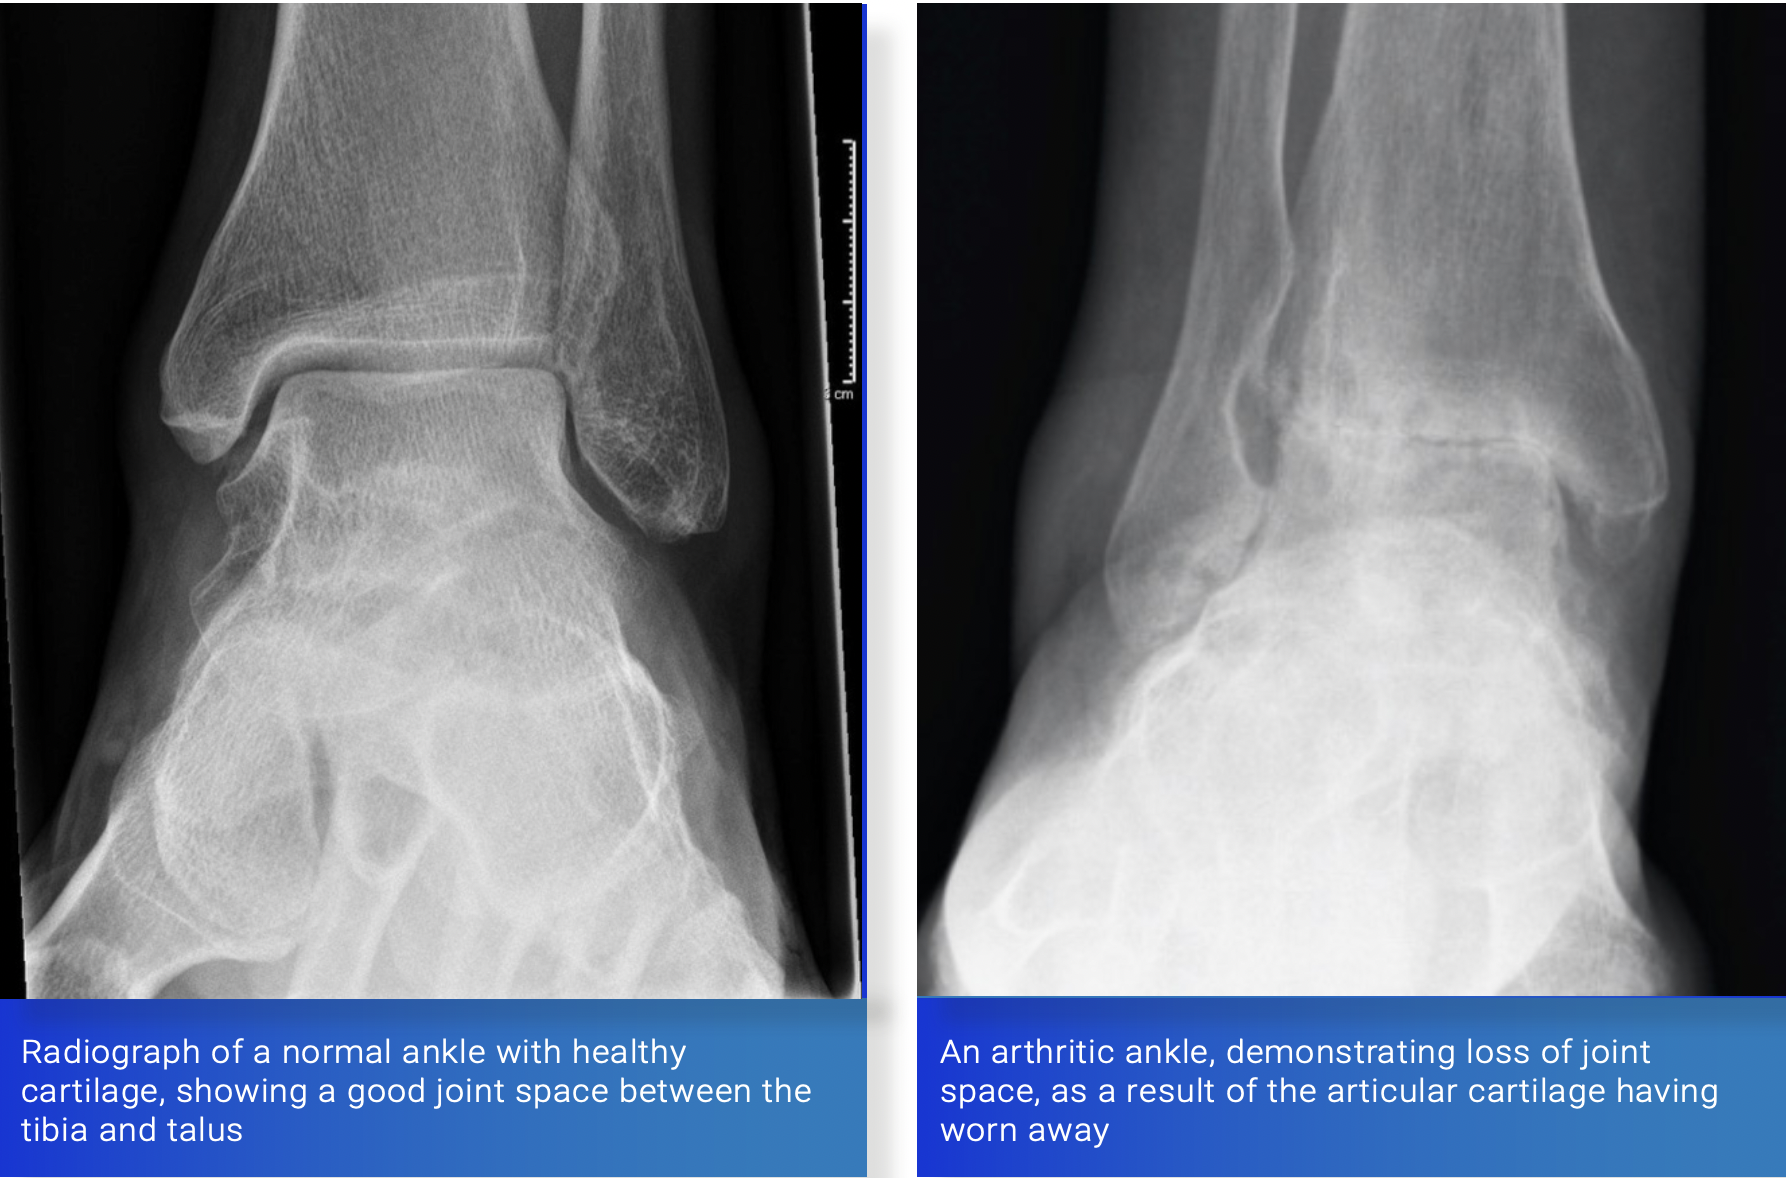

A normal synovial joint, such as the knee or ankle, is a complex structure that allows pain free, low friction movement. It relies on the joint surfaces being a perfect fit for one another (congruence) as well as a low friction lining (cartilage).

The hyaline cartilage that lines a synovial joint is a highly specialised substance with unique properties. It has a very low coefficient of friction, allowing smooth joint movement. The body is unable to produce hyaline cartilage and repairs injury with fibrocartilage. This is a less resilient, higher friction form of cartilage not usually found in synovial joints and as a result is less effective in facilitating joint glide.